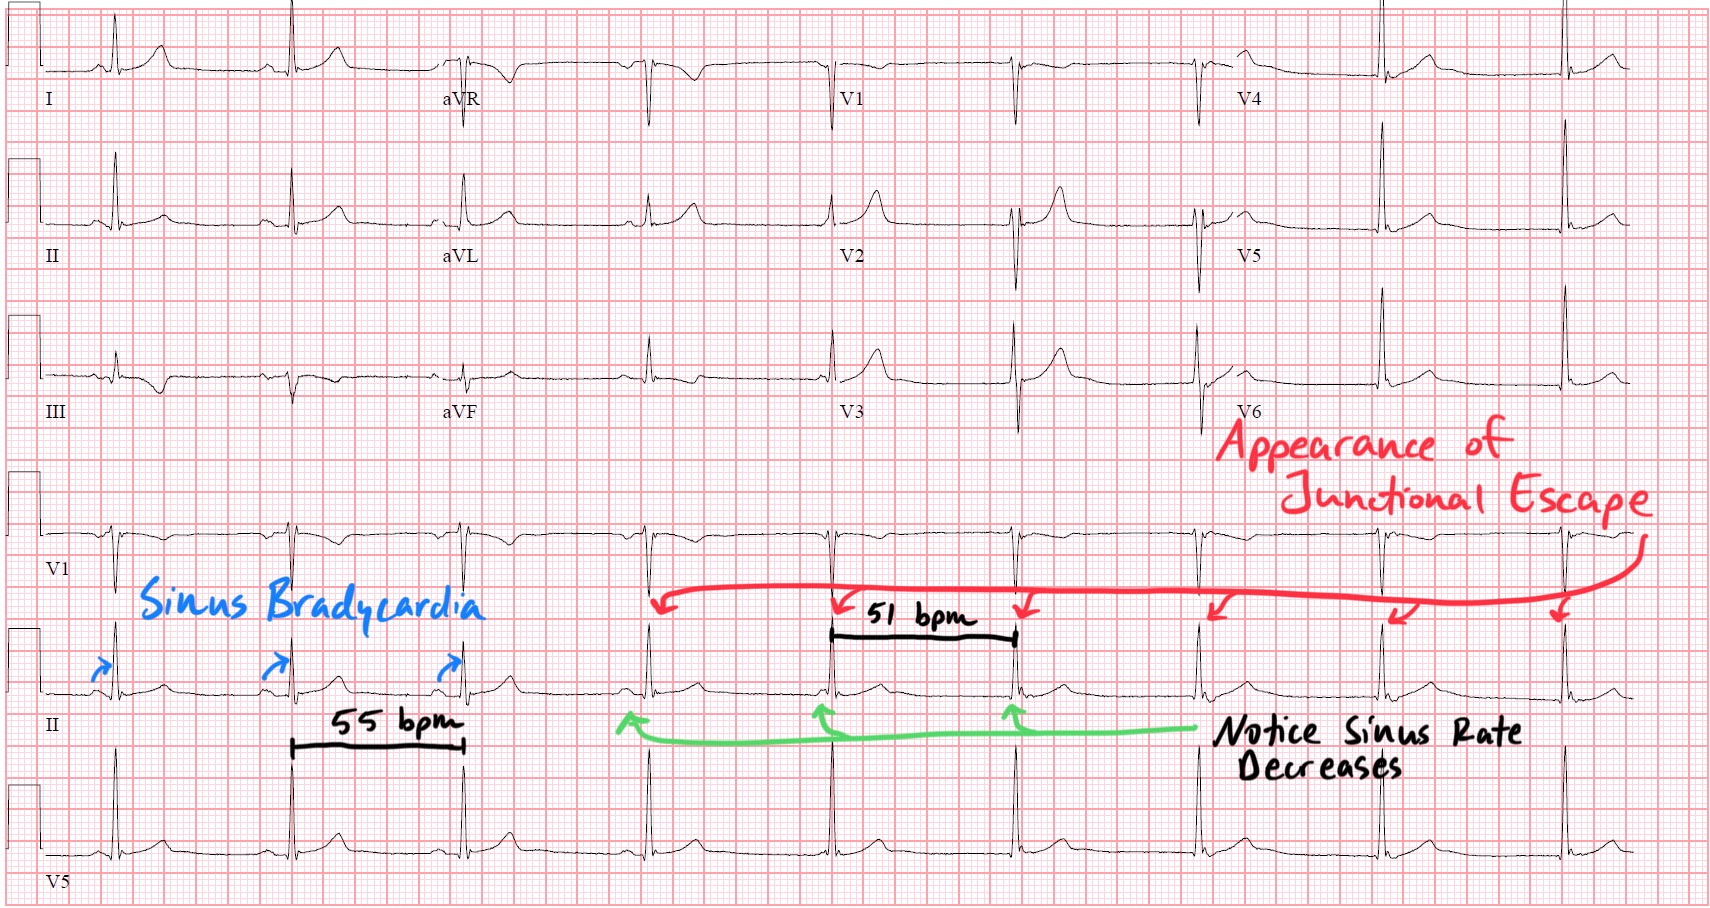

Isorhythmic AV Dissociation from Sinus Arrhythmia

Dec 06, 2025Isorhythmic AV dissociation is one of those ECG findings that looks more arcane than it actually is. At first glance, it can mimic AV block, retrograde atrial activation, or even a wandering pacemaker. But when you approach it through physiology—specifically, the competing intrinsic rates of the SA node and AV junction—the tracing becomes remarkably intuitive.

The most common clinical setting is sinus arrhythmia with vagally mediated SA node slowing. During normal respiration or heightened vagal tone, the SA node’s firing interval can lengthen just enough that it briefly relinquishes its leadership role. When that pause reaches the intrinsic escape interval of the AV junction, a junctional escape rhythmemerges—not because conduction is impaired, but because the timing simply favors the subsidiary pacemaker.

The result is dissociation without dominance: P waves wander across the QRS complexes, sometimes preceding them, sometimes falling inside them, and sometimes appearing just after. The atria and ventricles are not blocked from each other—they are merely out of sync by coincidence of rate.

PP intervals demonstrate respiratory variation, confirming the sinus node is slowing and accelerating in a predictable pattern.

QRS complexes remain narrow, signaling that ventricular activation is originating from a stable junctional focus rather than from aberrancy.

The P–QRS relationship shifts beat to beat, reflecting two clocks with nearly identical but not identical rates.

The critical distinction—especially for physicians confronted with bradycardia—is that this is not an AV block. Conduction is intact; the physiology is rate competition. The SA node is simply firing too slowly for brief intervals, allowing the junction to express itself until sinus rate rises again and reclaims control.